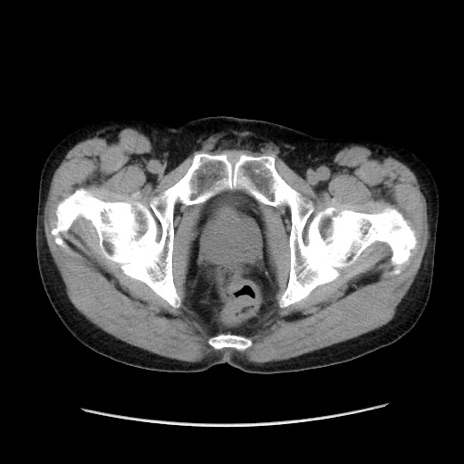

冠状断像

【症例】40歳代 男性

【主訴】腹痛

【現病歴】4時間ほど前に電車に乗車中に臍部上より腹痛出現。徐々に増悪し起立困難となり、救急外来受診。生ものは数日食べていない。今朝お雑煮を食べた。

【身体所見】BT 36.8℃、BP 117/84mmHg、HR 91/min、SpO2 97%、苦悶様、腹部:臍上部広範囲圧痛あり、反跳痛±

【データ】WBC 8100、CRP 0.03